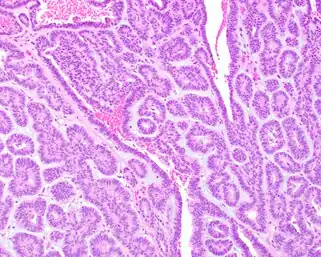

Histologicamente, o adenoma canalicular é caracterizado por ser uma neoplasia benigna composta por epitélio cuboide ou colunar formando canalículos, dispostas em ilhotas ou cordões de células com espaços císticos entre esses cordões.[1] Esse tumor pode infiltrar a cápsula e até mesmo formar tumores microssatélites extracapsulares.[1] O estroma tumoral é composto por tecido conjuntivo frouxo bem vascularizado.[1][2]

Em alguns casos, pode haver focos de células basaloides ou oncocíticas, assim como metaplasia mucinosa.[1][2] No estroma é possível encontrar histiócitos e focos de degeneração ou hemorragia.[1][2]

Necrose é excepcionalmente encontrada, assim como mitoses, estando normalmente ambas ausentes.[1][2] Não há registros de transformação maligna deste tumor, mas ele é ocasionalmente reportado como um tumor híbrido ou de colisão com outra neoplasia.[1][2][5]